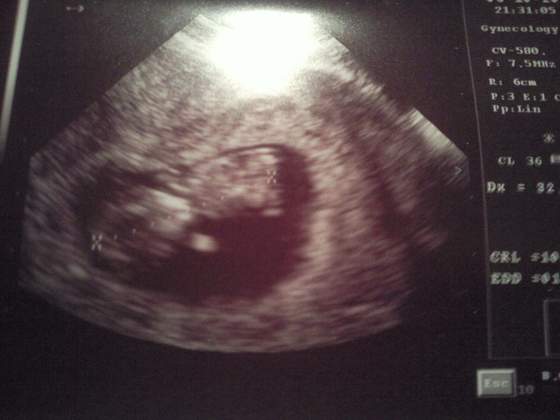

potem zaczelo mnie mdlic i to fest i zaczelo mi sie robic slabo jak nigdy mysle holera o co chodzi polecialam do kibelka bo myslalam ze bede zwracac ale tylko powietrze mi sie odbijalo z odruchem wymiotnym , spojrzalam w lustro